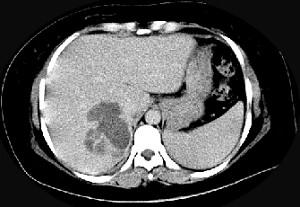

问题 女,36岁,右上腹痛,有发热,白细胞计数升高,CT检查如图,最可能诊断是 ( )

选项 A、肝黄色肉芽肿 B、肝胆管细胞癌 C、肝淋巴管瘤 D、肝脓肿 E、原发性肝癌

答案 D